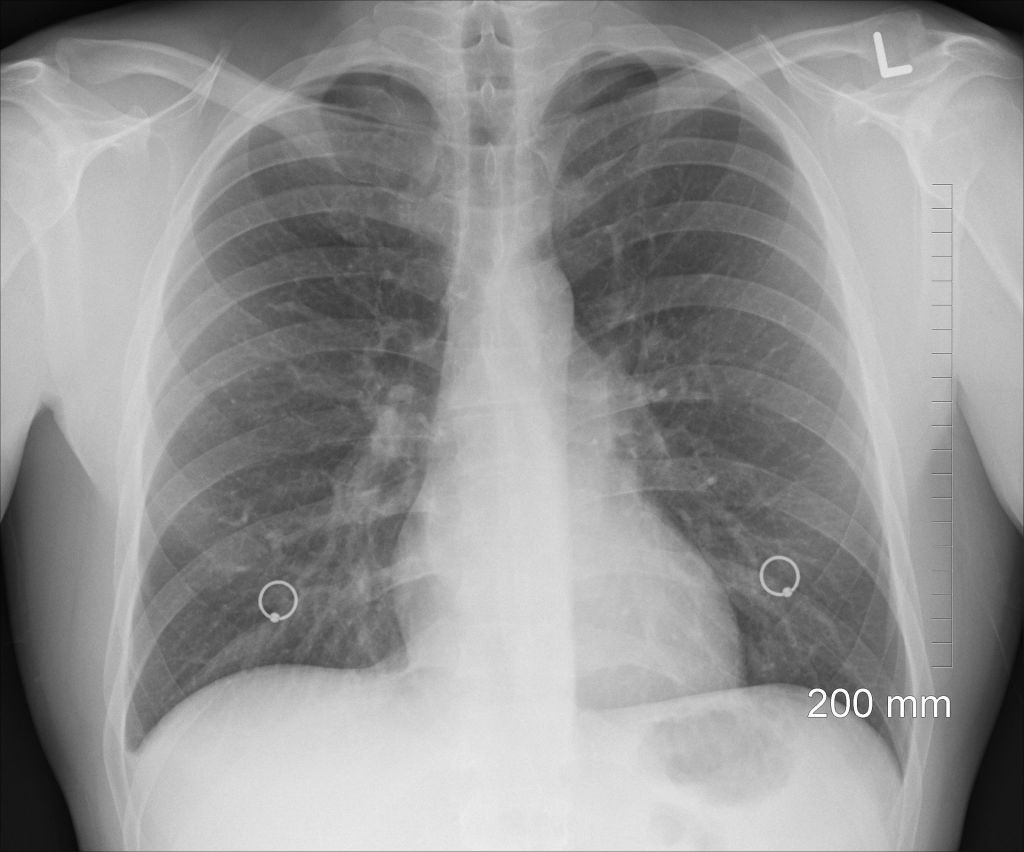

4Daños pulmonares

El tipo de neumonía que con frecuencia se asocia con el covid-19 puede causar daño duradero a los diminutos sacos de aire (alvéolos) de los pulmones. El tejido cicatricial resultante puede llevar a problemas respiratorios a largo plazo.

En un estudio de 55 pacientes con covid-19, a los tres meses de haber sido dados de alta, el 64% presentaban síntomas persistentes y el 71% presentaban anomalías consistentes con una disfunción pulmonar.

En otra investigación de 57 pacientes, las anomalías en los resultados de las pruebas de función pulmonar obtenidos 30 días después del alta revelaron que lo más común era la disminución de la capacidad de difusión del monóxido de carbono (53%) y la perdida de fuerza de los músculos respiratorios (49%).

Las secuelas más comunes son similares a algunos de los síntomas de la fase aguda de la enfermedad: falta de aliento, tos y presión en el pecho.